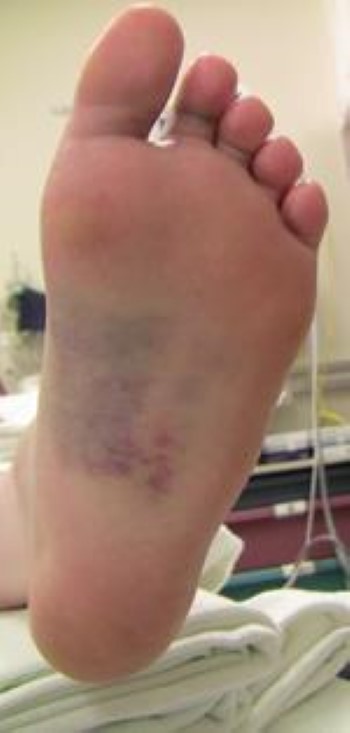

• There may be bruising on both the top and bottom of the foot. Bruising on the bottom of the foot is highly suggestive of a Lisfranc injury.

Bruising on bottom of foot

The discoloration on the bottom of the foot is very suggestive of a Lisfranc injury.

• Bruising along the bottom of your foot. This suggests a complete tear of the midfoot ligaments or a midfoot fracture.